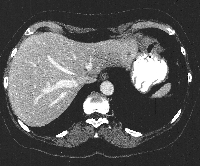

Πρόκειται για γυναίκα ασθενή 57 ετών, η οποία υποβλήθηκε σε γαστροσκόπηση για άτυπα γαστρεντερικά συμπτώματα. Διαπιστώθηκε επίπεδη βλάβη στην περιοχή του ελάσσονος τόξου στο σώμα του στομάχου. Από την ιστολογική εξέταση της συγκεκριμένης περιοχής διαπιστώθηκε γαστρικό αδενοκαρκίνωμα. Επιπλέον, η αξονική τομογραφία σταδιοποίησης ανέδειξε, στο 2ο ηπατικό τμήμα, ενδοπαρεγχυματική μονήρη μάζα μεγέθους 1 cm, παρακειμένως της γαστρικής βλάβης (εικόνα 1). Η ασθενής υποβλήθηκε σε υφολική γαστρεκτομή και σε en bloc εκτομή του 2ου ηπατικού τμήματος. Διενεργήθηκε λεμφαδενικός καθαρισμός (εικόνα 2) του τρίποδα του Haller (LNst 9), της αριστερής γαστρικής (LNst 7) και της ηπατικής αρτηρίας (LNst8). Επιπλέον, η άνω μεσο-εγκάρσια περιτονία (η καλύπτουσα την άνω παγκρεατική επιφάνεια) συμπεριλήφθηκε στο παρασκεύασμα (εκτομή D2). Πραγματοποιήθηκε εντερική αποκατάσταση κατά Billroth II (εικόνα 3). Η ασθενής έλαβε εξιτήριο τη 10η μετεγχειρητική ημέρα.